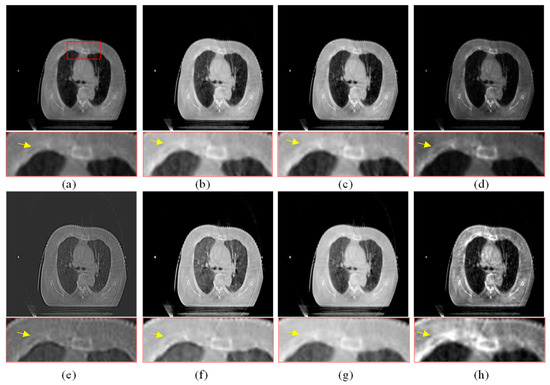

Figure 9.

Enhanced results of pair 3. (a) Source CBCT images. (b) MSR. (c) MSRCR. (d) DCP. (e) CBF. (f) RRM. (g) SMIPC. (h) Ours.

The same conclusion can also be obtained in Figure 9 and Figure 10. Especially in the enalrged region in Figure 10, our results provide a much clearer organizational structural and edge infromation, which is very helpful for disease diagnosis and treatment. Through comparison, it can be found that the rigidity informaiton in our results is more significant, the tissue edge in our results is clearer, and the contrast of the texture structure is also better than that of the comparison algorithms. The observation effect is greatly improved by our enhancement method, proving that our method can effectively enhance the CBCT images.